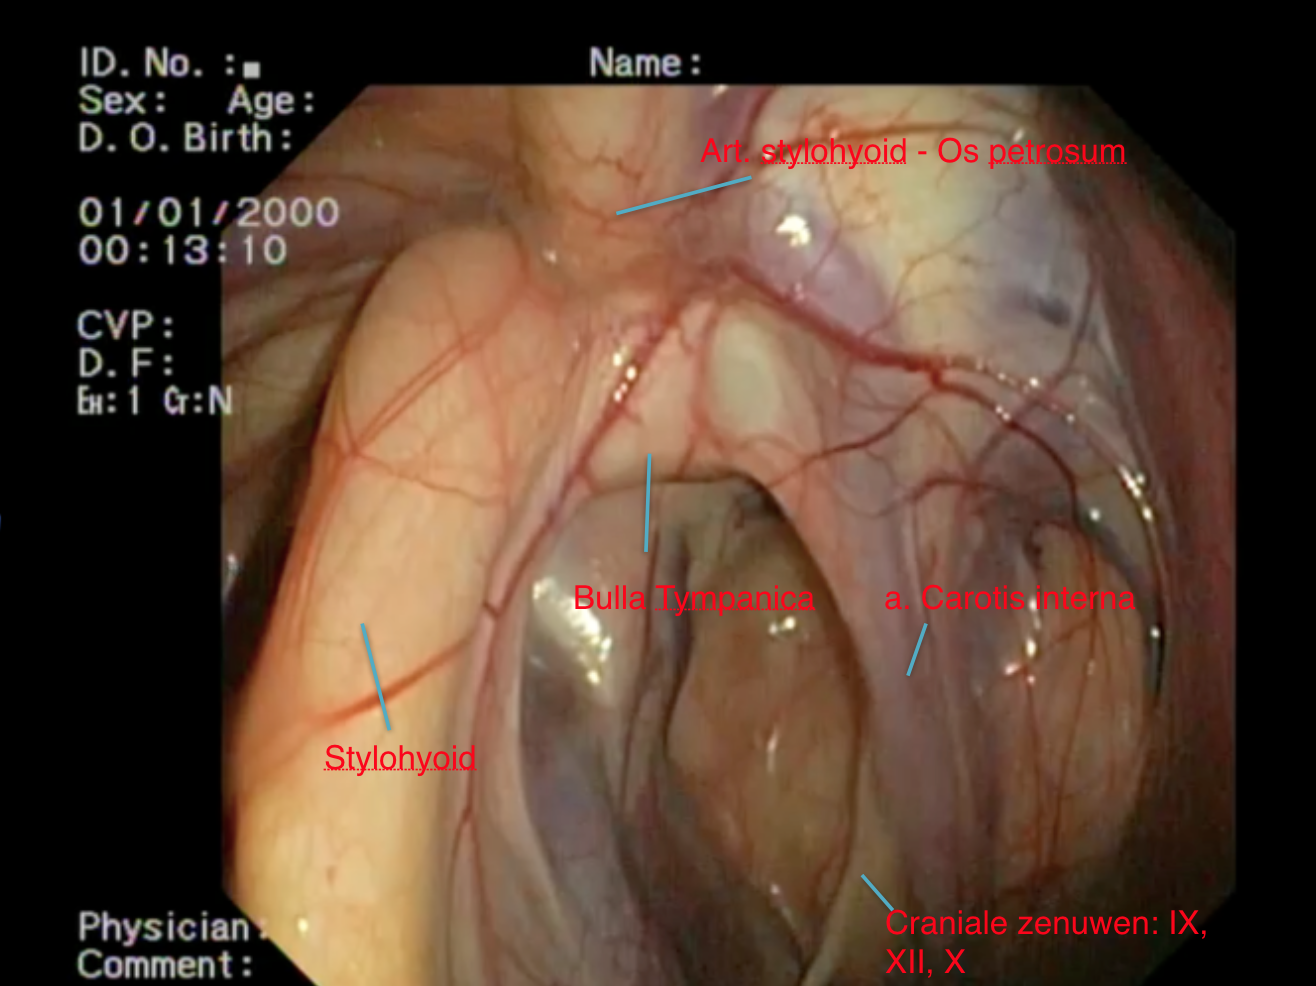

Některé z hlavních cév zásobujících hlavu se nacházejí v těsné blízkosti stěn vzdušných vaků. Jedná se zejména o hlavní tepnu (krkavici), která vystupuje přímo ze srdce a zásobuje kyslíkem hlavu a mozek. Na úrovni hlavy se tato tepna rozdělí do několika silných tepenných větví, které procházejí stěnami vzdušných vaků (vnější a vnitřní větev krkavice a čelistní tepna, obr. 2).

Hlavové nervy vybíhají z mozkového kmene a inervují struktury v blízkosti hlavy. Je jich celkem dvanáct. Některé z těchto nervů (IX, X, XII) procházejí vzdušnými vaky a mohou při mykóze vaků způsobovat typické neurologické potíže. Jazykohltanový nerv (IX) inervuje svaly jazyku a hrdlo. Bloudivý nerv (X) je velmi důležitý nerv, který inervuje velké svaly, jako jsou hlasivky a svaly hrtanu. Podjazykový nerv (XII) inervuje mimo jiné i jazyk (obr. 2).

Jakmile se plíseň rodu Aspergillus uchytí ve vzdušných vacích, nalezne zde ideální místo k množení. Plísně mají rády teplo, a proto se obvykle usídlují v blízkosti velkých krevních cév, které vedou vzdušnými vaky. Tyto tepny jsou pro plísně zároveň ideálním zdrojem živin. Nejčastěji se plísně nacházejí v blízkosti vnitřní větve krkavice (obr. 3 a, b, obr. 4).